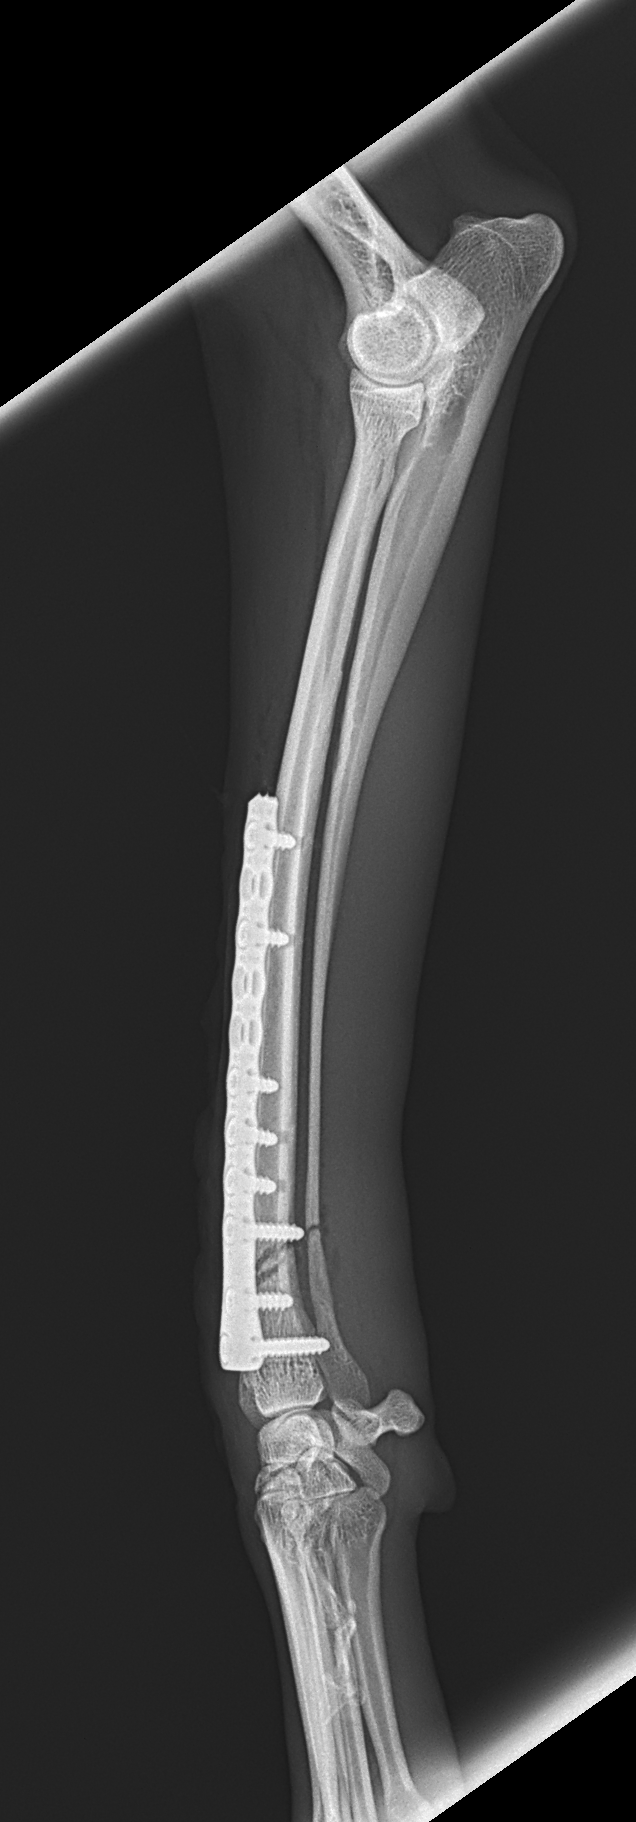

橈骨固定術 #239

イタリアングレーハウンドがジャンプした後から跛行しているとの事。2.4 Locking Plateで固定術を行いました。しばらくはインプラントにロードベアリングしているため骨がロードシェアできるまでは初期固定強度を担保するために外固定の併用を行います。